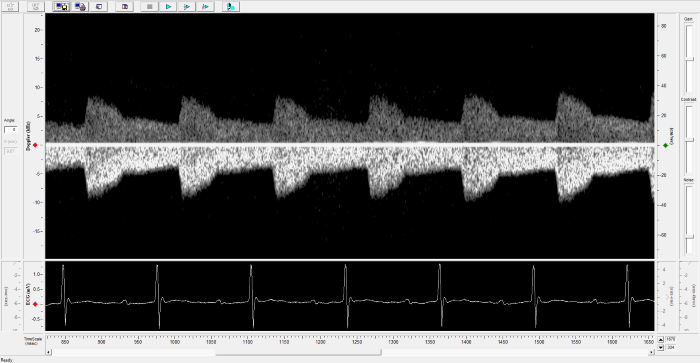

Rat - Left Carotid

Rat - Left Carotid. Image Credit: Scintica Instrumentation Inc.